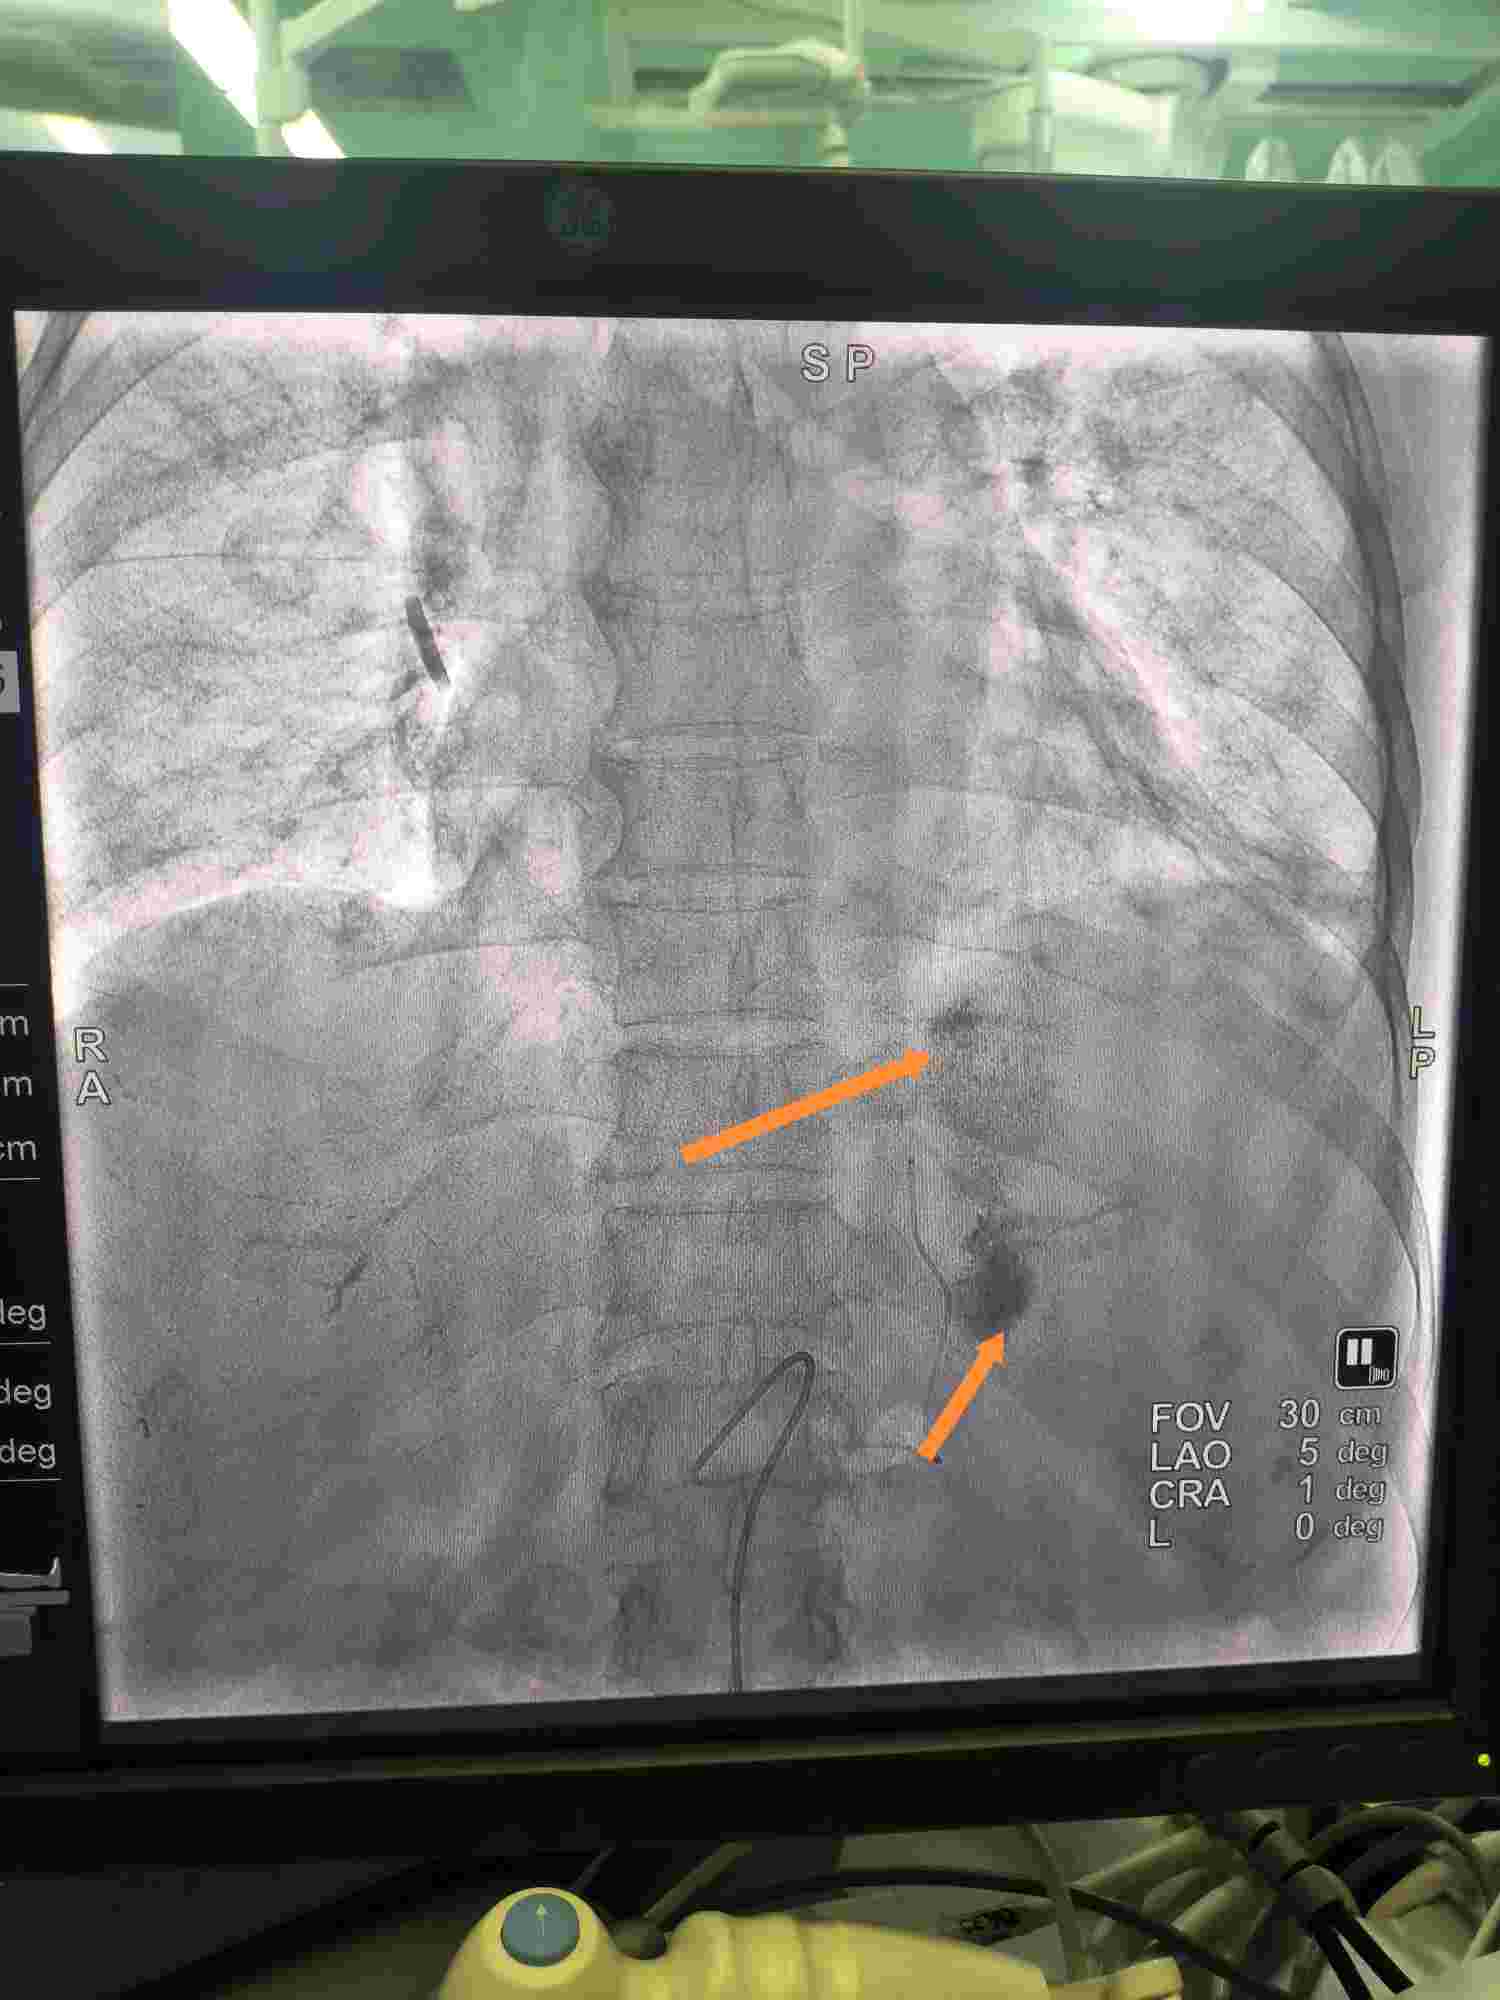

脾动脉造影肿瘤染色明显

栓塞后碘油沉积